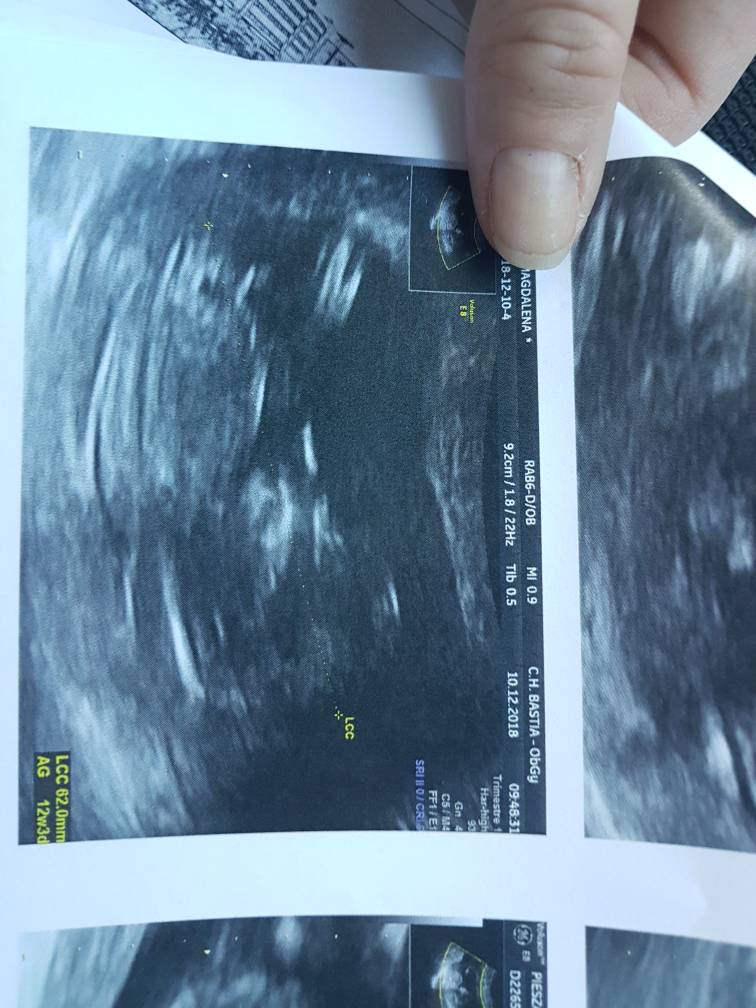

Jest okDziewczyny wszystko dobrze jest .... dzieciaszek 6,5 cm przyziernosc 1,8 później dam fotkę .... czy przyziernosc jest ok? 12+3?

Tu chyba widać ten wyrostek i wydaje mi się że to chłopakPoznajcie moja dzidzie[emoji7][emoji7][emoji7] mam wrażenie ze to chłopiec nie wiem czemuZobacz załącznik 923676

Tak, wyrostek jest skierowany do góry więc faktycznie raczej chłopczyk!!Poznajcie moja dzidzie[emoji7][emoji7][emoji7] mam wrażenie ze to chłopiec nie wiem czemuZobacz załącznik 923676

Powiedz mi gdzie tu tu cokolwiek rozrozniasz ? [emoji16] ja to chyba jestem slepa i nic nie widze na tych wszystkich zdjeciach usg [emoji16]Tak, wyrostek jest skierowany do góry więc faktycznie raczej chłopczyk!!) śliczny!

No jest taka kreska biała na wysokości kręgosłupa i później druga wyżej - w miejscu narządów płciowych- ta druga jest skierowana do góry co wskazuje na chłopcaPowiedz mi gdzie tu tu cokolwiek rozrozniasz ? [emoji16] ja to chyba jestem slepa i nic nie widze na tych wszystkich zdjeciach usg [emoji16]